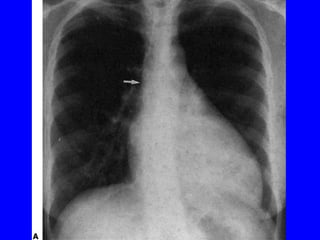

Signes radiologiques de l’IAo

IAo aiguë

• Rx: Signes congestifs , Volume cardiaque

normal.